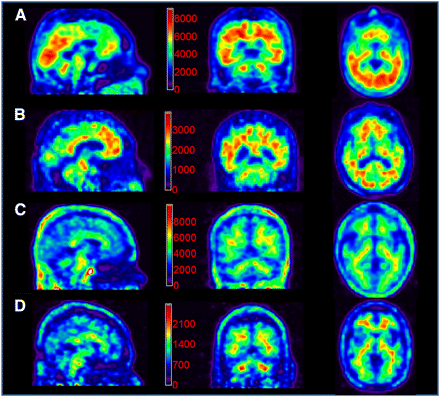

Figure 1. Labeling of Brain Aβ Deposits with 18F-florbetapir. Reproduced from (44) with permission. © 2012 Society of Nuclear Medicine and Molecular Imaging (SNMMI).

There was also some suggestion of a reduction in brain Aβ deposits in solanezumab-treated volunteers with mild AD, as measured using the PET tracer 18F-florbetapir.(7,8) This result was at P=0.10, but the lack of statistical significance may reflect underpowering rather than statistical noise, because only a subset of volunteers underwent florbetapir-PET. Additionally, there was a substantial increase in total CSF Aβ42 and -40 in treated subjects, and a dose-dependent increase in CSF free Aβ42 in subjects administered 400 mg/d.(11) In addition to indicating target engagement by solanezumab, the rise in CSF Aβ42 is consistent with a postitive therapeutic effect, since CSF Aβ42 is consistently observed to decline during the period leading in to AD diagnosis.

There is an additional aspect of the PET and CSF biomarker data that suggests that the original EXPEDITION trials may have diluted the potential benefit of solanezumab because of inaccurate patient diagnosis and recruitment. The volunteers recruited for those trials had been diagnosed with AD based entirely on clinical criteria, but fluorbetapir-PET testing of a subset of participants revealed that 26% of tested subjects had no amyloid pathology.(7,8) This suggests that many of the subjects’ cognitive impairments were not driven by Aβ, but by other causes such as frontotemporal or vascular dementia. In such subjects, any effect of an Aβ-targeting therapy would be be expected to be much more limited than in subjects with AD as a disease of Aβ, suggesting that the true treatment benefit in subjects with (mild) AD may have been greater than was reported. As a result, EXPEDITION-3 will recruit only subjects with an AD diagnosis confirmed to be amyloid-associated with PET or CSF data.